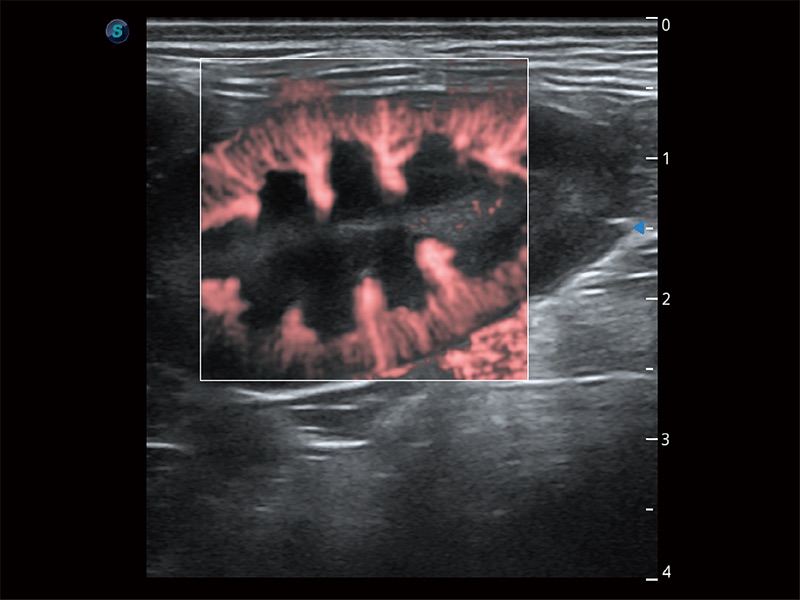

• Bright Flow 立体血流成像

在传统二维血流成像的基础上,呈现血流的立体感,具有动感的生命力之美。即便是微小的血管也能轻松应对,提高了血流的视觉敏感性。

(犬)肾脏显微血流